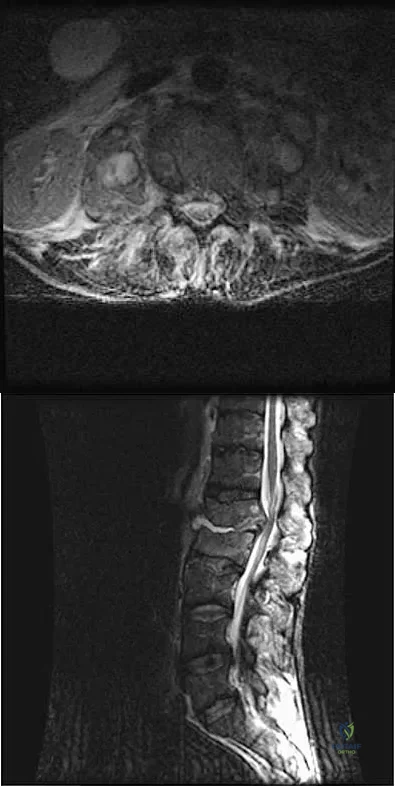

A patient who has had neck pain radiating down the arm for the past 4 weeks reports that the pain was excruciating during the first week. Management consisting of anti-inflammatory drugs and physical therapy has decreased the neck and arm symptoms from 10/10 to 3/10. He remains neurologically intact. MRI and CT scans are shown in Figures 5a and 5b. The best course of action should be

A 78-year-old woman undergoes her third lumbar decompression and fusion from L3 to L5 without complication. On the morning of postoperative day 3, examination reveals painless, flaccid weakness of both lower extremities. She also has an absent bulbocavernous reflex and a mild saddle paresthesia. MRI scans of the lumbar spine are shown in Figures 26a and 26b. What is the most appropriate management at this time?

A 32-year-old man notes increasing back pain and progressive paraparesis over the past few weeks. He is febrile, and laboratory studies show a WBC of 12,500/mm3. MRI scans are shown in Figures 6a and 6b. Management should consist of